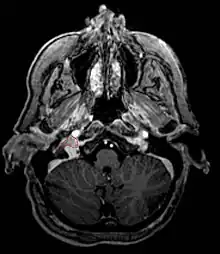

Paragangliome

Paragangliome du glomus jugulaire